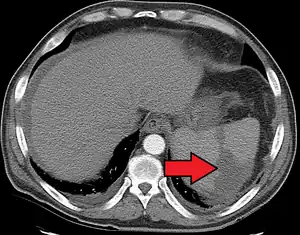

a, b) Splenic infarction.

Splenic infarct seen on CT

Although it can occur asymptomatically, the typical symptom is severe pain in the left upper quadrant of the abdomen, sometimes radiating to the left shoulder. Fever and chills develop in some cases.[3] It has to be differentiated from other causes of acute abdomen.

An abdominal CT scan is the most commonly used modality to confirm the diagnosis,[3] although abdominal ultrasound can also contribute.[16][17][18]